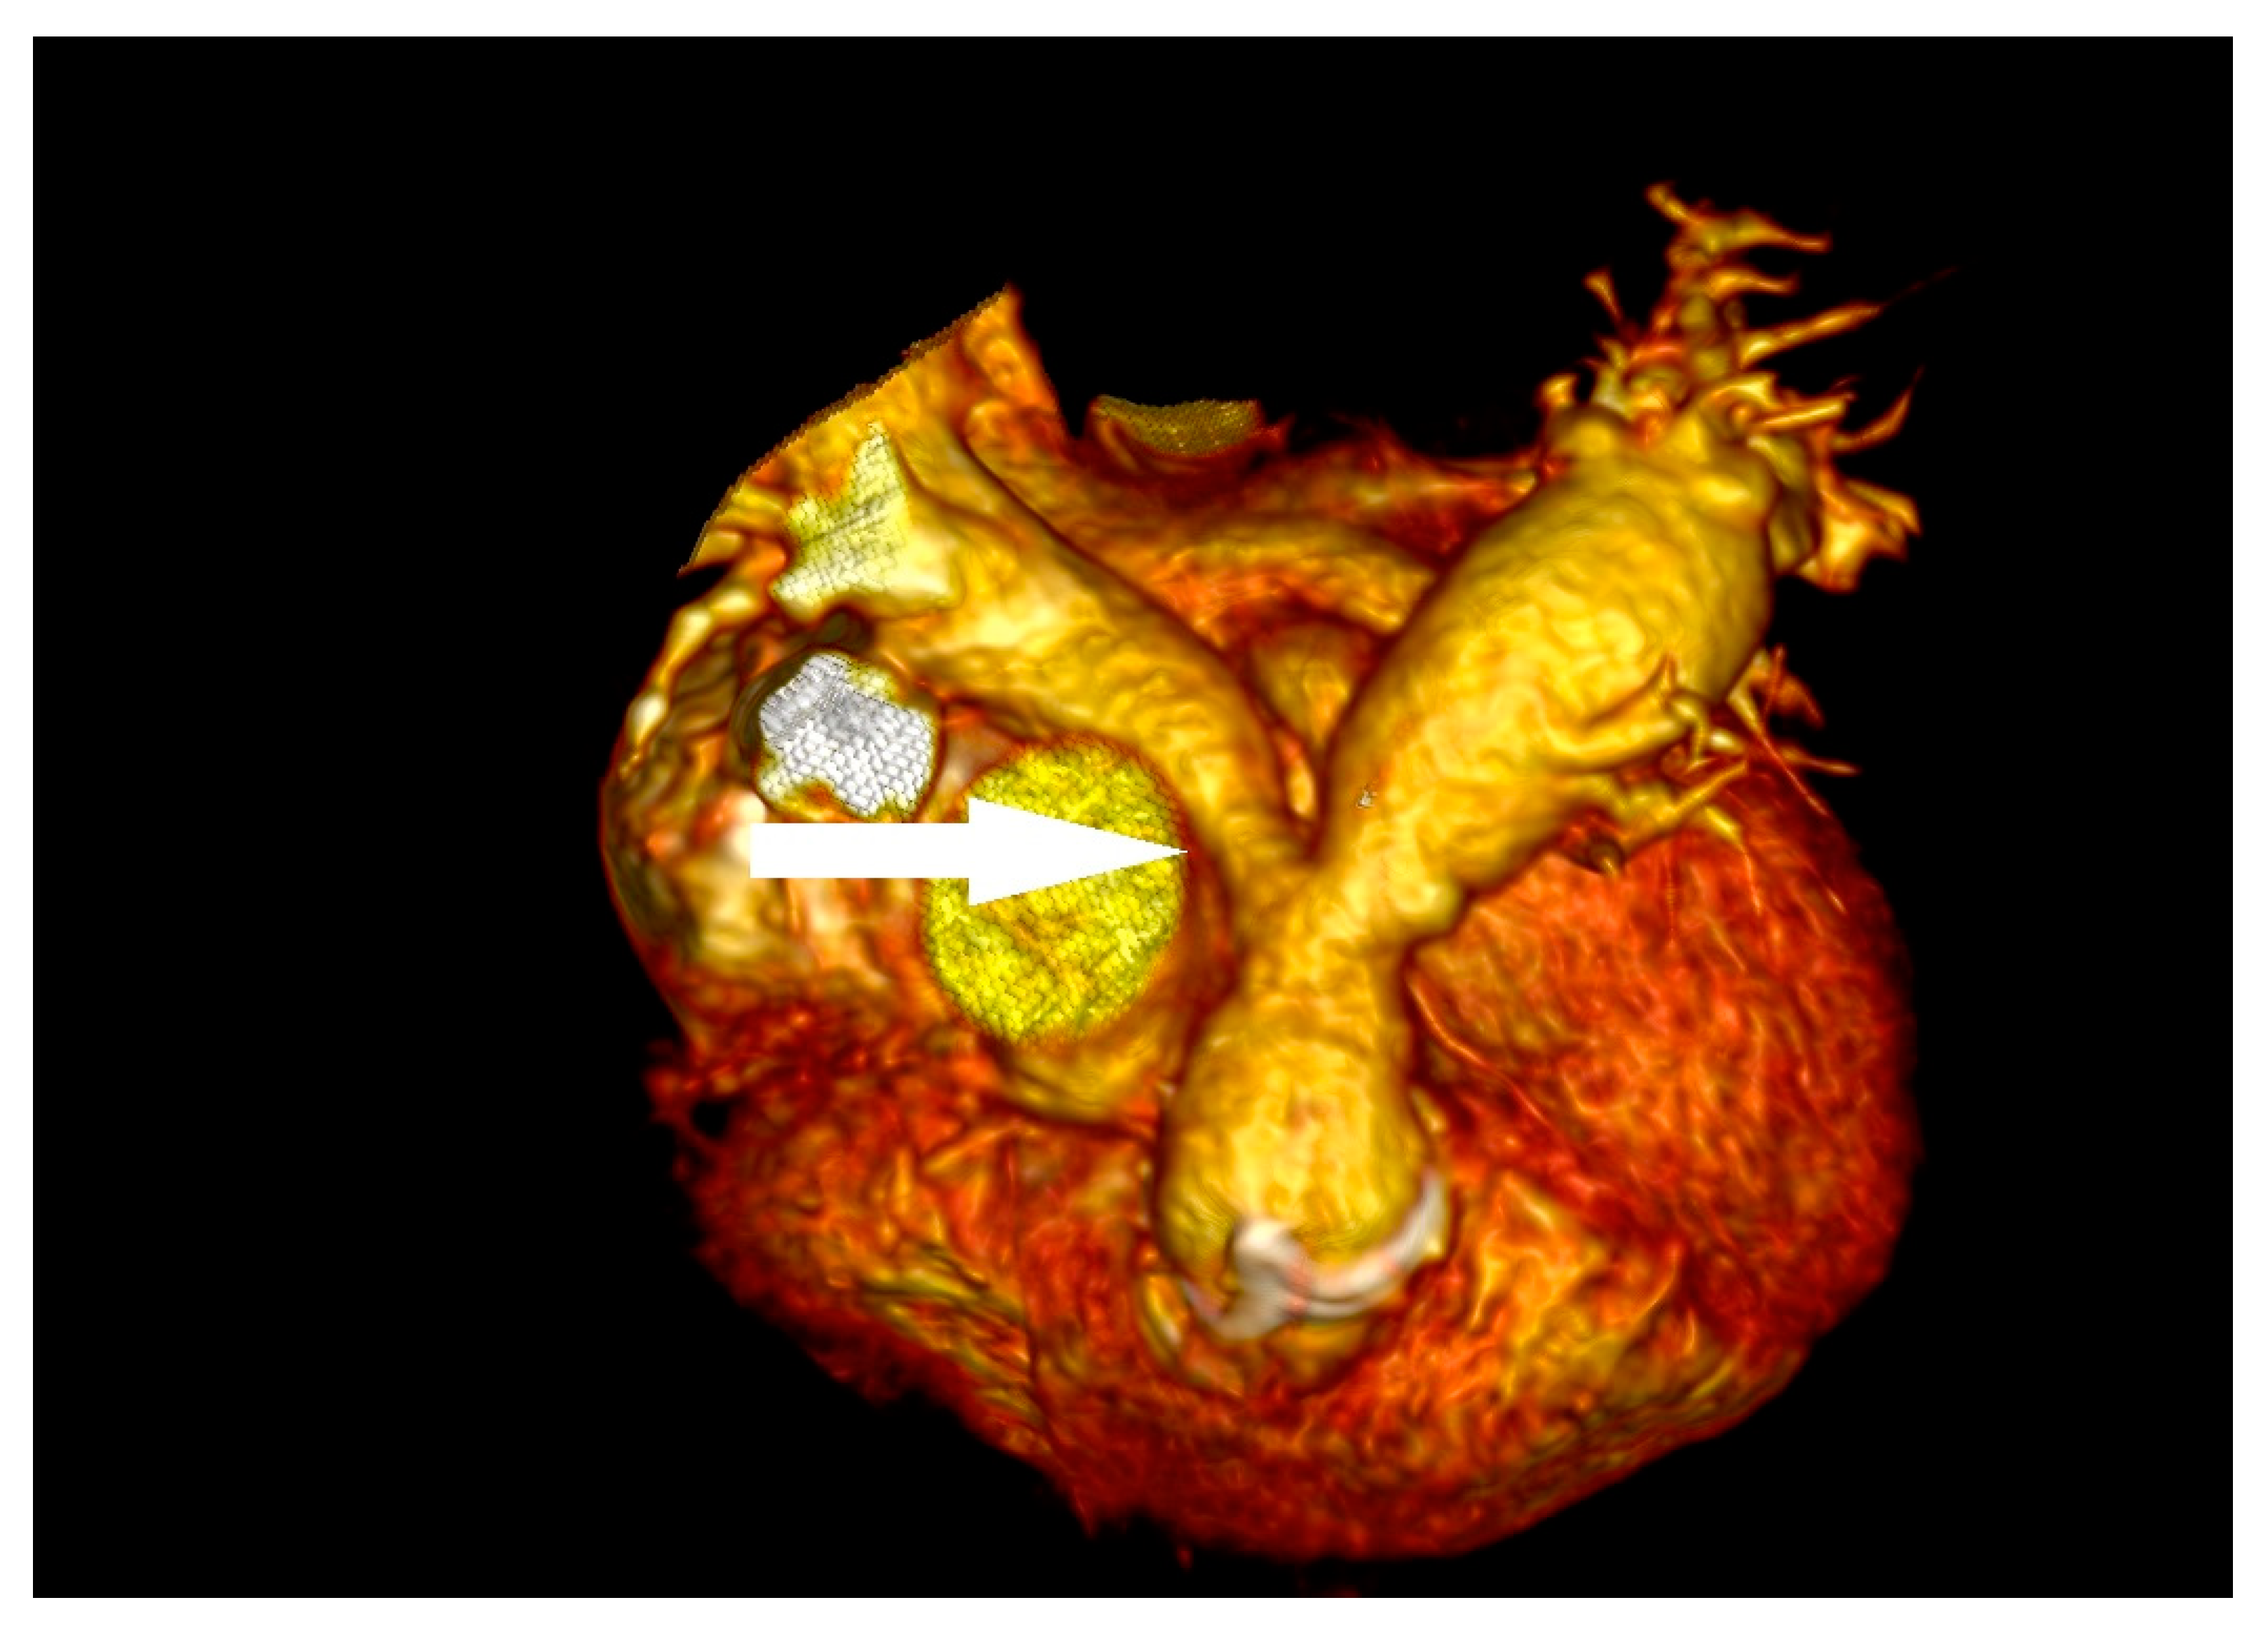

A 14-year-old boy with mild intellectual disabilities was admitted to the hospital because of left spastic hemiparesis, facial nerve palsy, and slurred speech. Apart from neurological symptoms, the clinical examinations revealed a systolic heart murmur of 2/6 in LS. A central nervous system ischemic stroke was confirmed in imaging tests, and the bicuspid aortic valve with ballotable vegetation and moderate regurgitation were found in TTE (Figure 8), subsequently confirmed by TOE.

Figure 8.

The vegetation in the bicuspid aortic valve before cardiac surgery.

The CRP level (164.4 mg/L) and other inflammatory indicators were temporarily elevated, which was related to a vascular access inflammatory reaction. All the results of blood culture samples taken according to the ESC procedure were negative. Acetylsalicylic acid (150 mg/day), enoxaparin (40 mg/day), vancomycin (firstly 1.5 g, twice/day for 7 days, next 1 g, twice/day for 10 days), and gentamicin (laboratory antibiotic concentration monitored) were administered as the treatment. In summary, the patient met one major and two minor Duke’s criteria, suggesting the possibility of IE. After nearly four weeks of treatment, papular eruption in the left thigh, hip, and arm and vomiting were observed. Moreover, reduced eGFR (24.90 mL/min/1.73 m2) and elevated levels of creatinine (3.59 mg/dL), urea (74.0 mg/dL), NT-proBNP (5762.5 pg/mL), and again CRP (97.40 mg/L) were observed. The antibiotics were replaced by sulfamethoxazole-trimethoprim (480 mg twice/day) and furosemide (20 mg/day for three days) was also administered. Very severe aortic regurgitation and normal left ventricular ejection fraction were obtained from repeated TTEs. Due to the patient’s deteriorating clinical condition, ceftriaxone (2 g/day) was administered in the treatment. The re-performed results of blood culture samples were negative and the patient’s clinical state was stable, making him urgently qualified for cardiac surgery. The native valve was replaced with a mechanical Bicarbon Fitline valve. The histopathology of the native aortic valve showed inflammatory cells infiltration. The patient remains under outpatient neurological, rehabilitation, and cardiological care.